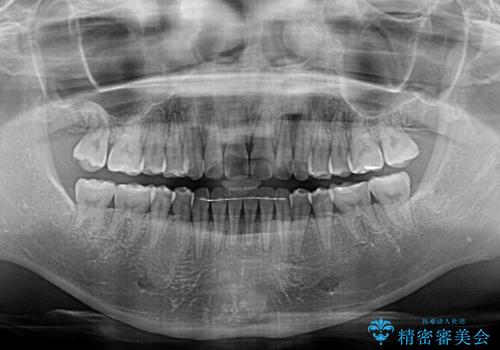

カリエールディスタライザーを併用したことで、確実かつ短期間で治療を終えることができました。